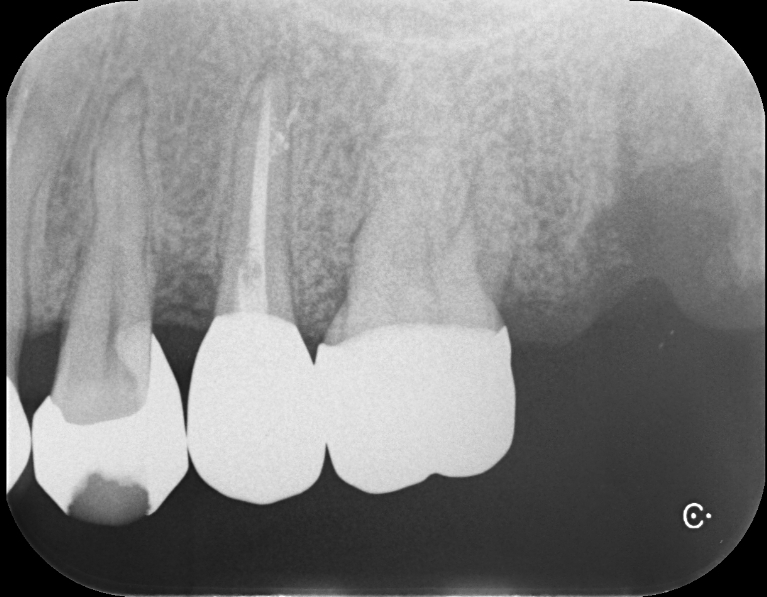

Case3

術前

術中

術後

根面被覆

| 治療名 | 前歯インプラント、根面被覆 |

|---|---|

| 治療説明 | 前歯4本の抜歯が必要となったためインプラントで回復することになりました。右上1,左上1に抜歯と同時にインプラントを埋入しました。右上2、左上2は結合組織移植を行いボリュームを回復することで、見た目と清掃性を向上させました。左右側方歯には根面被覆術を行って歯肉退縮を回復しました。 |

| 治療回数・期間 | 1年 |

| 副作用とリスク | インプラント治療は入れ歯やブリッジと比べて治療期間が長くかかることがあります。インプラント手術と結合組織移植は、違和感、痛み、腫れ、出血などが発生する場合があります。一時的なもので、2日〜1週間で治まります。 |

| 料金(税込) | 骨造成:110,000円(2本:220,000円) インプラント1次手術:220,000円(2本:440,000円) インプラント2次手術:55,000円(2本:110,000円) 結合組織移植:110,000円(4本:440,000円) 上部構造:220,000円(4本:880,000円) 根面被覆:396,000円 合計:2,456,000円 |